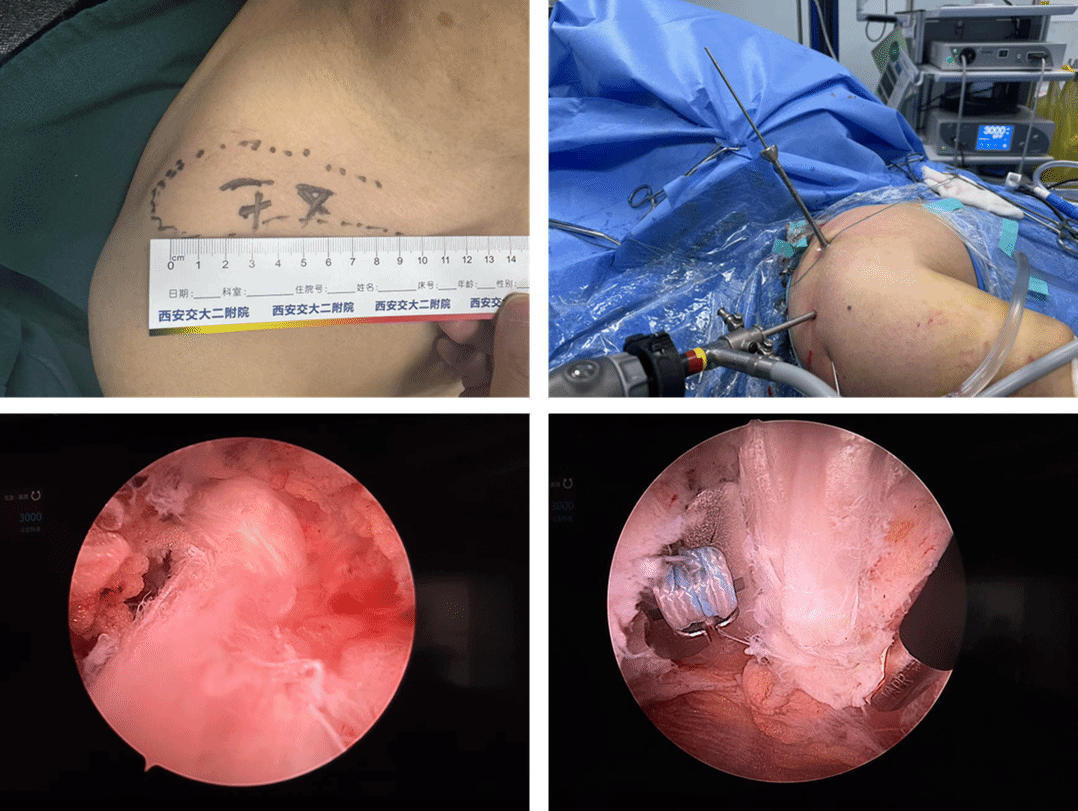

倪建龙团队根据患者病情,创新性设计了“三袢V形动力性重建术”。手术通过微创路径在患者锁骨处开2个不足2厘米的小切口;运用可调袢悬吊系统,锁骨及喙突处植入3个纽扣袢板,高强线呈V形连接喙突与锁骨双骨道,构建三角力学支架;进行活体韧带再生,取患者自体股薄肌肌腱,呈“8字”缠绕喙突与锁骨。

术中,根据完善的术前设计,倪建龙主刀,吕雷锋博士辅助,成功为患者王先生完成了陈旧性肩锁关节脱位的创新手术。倪建龙谈到,此次手术中,采用微创技术避免了肌肉剥离,患者术中出血不足50ml,有助于患者恢复;移植的肌腱在六周后会转化成韧带组织,发挥永久稳定作用;患者无需二次手术取出植入物,达到了永久治愈的治疗效果。